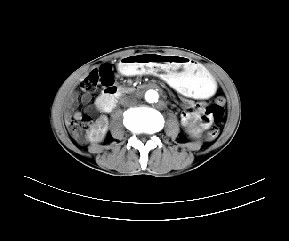

标题: CT19533:病变来源于哪?

患者,男,发现上腹部包块两月余。

病变位于肝胃间隙,实际就是位于小网膜囊(左肝下后间隙),呈轻度不均匀性强化,腹腔内及腹膜后见多发肿大淋巴结。所以我考虑肝胃间隙恶性胃肠间质瘤并淋巴结转移。

病灶强化不显著,灶周及腹膜后见多量淋巴结肿大,考虑淋巴瘤可能,其次考虑间质瘤

病灶与胰腺分界不清,来源于胰腺?

强化后病变与胃壁分界清楚,并且血供不是来源胃壁血管。考虑胰腺颈体癌并腹腔腹膜后淋巴结转移。